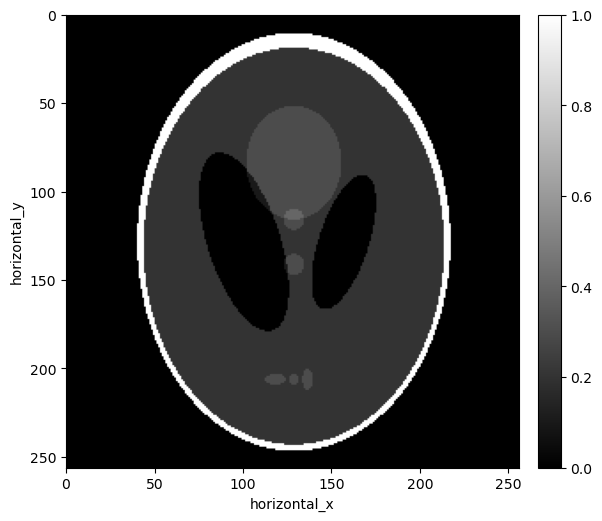

show2D([recon_wls_tv], ["WLS TV alpha=%7.6f, psnr = %7.5f" % (alpha,psnr_wls_tv_alpha[i])], \

cmap=cmap,fix_range=(0,1), size=(10,10), origin='upper-left')

../../_images/demos_LS_WLS_KL_TotalVariation_40_0.png

../../_images/demos_LS_WLS_KL_TotalVariation_40_1.png

alpha=0.000020, psnr= 18.611

alpha=0.000022, psnr= 19.630

alpha=0.000024, psnr= 20.455

alpha=0.000026, psnr= 21.108

alpha=0.000028, psnr= 21.611

alpha=0.000041, psnr= 22.762

alpha=0.000043, psnr= 22.781

alpha=0.000045, psnr= 22.778

alpha=0.000047, psnr= 22.758

alpha=0.000049, psnr= 22.725